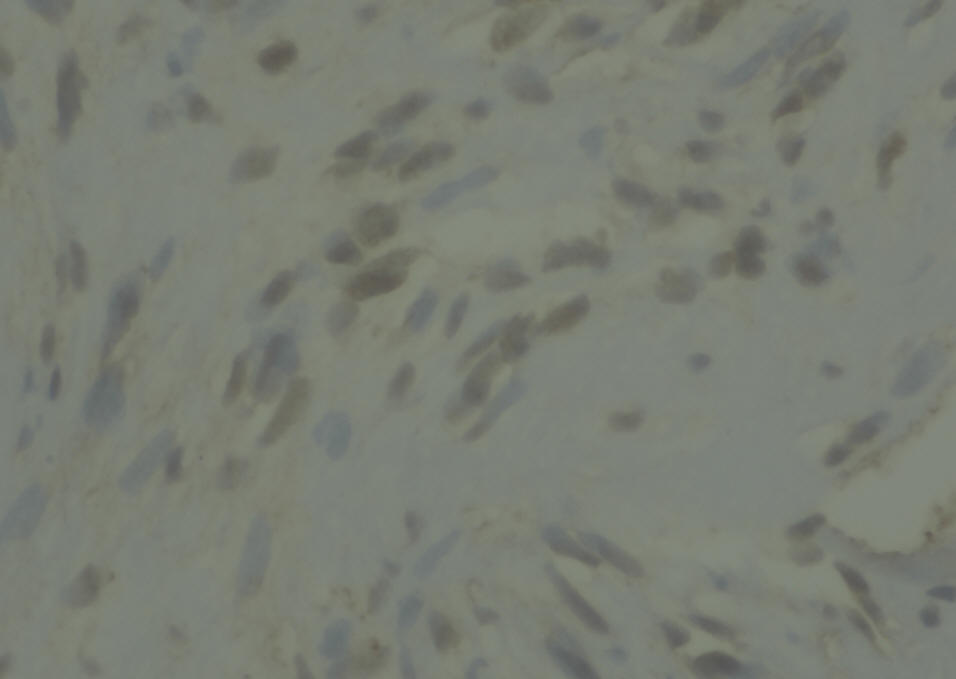

Sections show a circumscribed tumor composed of spindle cells displaying prominent nuclear palisading and Vercoy bodies. This lesion exhibits peripheral tongues extending into the brain cortical tissue. There is no evidence of mitotic activity, nuclear anaplasia or necrosis. Tumor shows heavy interstitial reticulin deposition and reacted positively to S-100 and Vimentin. Tumor did not react to GFAP and EMA. Proliferative index was estimated at 2%, but not exceed 3% in any area. There is no evidence of malignancy. Conclusion: Intracerbral schwannoma. ( Prof. Yahya F. Dajani Consultant pathologist. 29-January-2022.